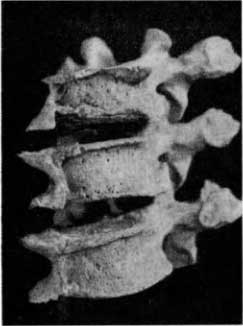

Заслуживает внимания соответствующая находка из погребений VI–XI столетий в Эски-Кермене (в Крыму). На трех смежных грудных позвонках видно довольно мощное окостенение передней продольной связки (рис. 47). При раскопках или при транспортировке окостеневшая связка, соединявшая тела позвонков, сломалась, поэтому эти позвонки разъединились. Если их сложить, то сломанные участки окостеневшей связки совпадают друг с другом. При этом легко убедиться, что высота межпозвонковых пространств не снижена, что напоминает соответствующие соотношения при болезни Бехтерева.

Описанные изменения обнаружены на позвоночнике пожилого человека с проявлениями деформирующего артроза на суставных фасетках всех поперечных отростков. У этого человека несомненно был старческий кифоз позвоночника, о чем свидетельствует клиновидная деформация тел представленных двух верхних позвонков. Высота их отчетливо снижается кпереди (рис. 47).

Рис. 47. Фиксирующий лигаментоз на трех грудных позвонках.